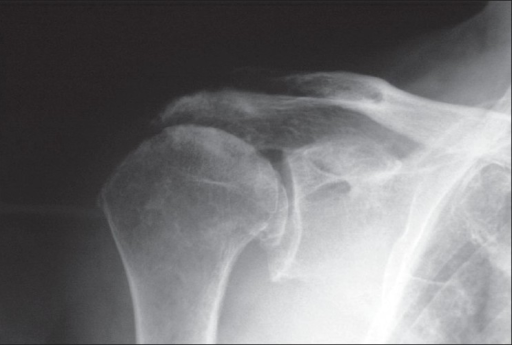

Osteoarthritis

• Osteoarthritis of the shoulder is much less common in comparison to osteoarthritis of the hips or knees

• It is none the less still a debilitating condition that can have a significant impact on a patient’s quality of life.